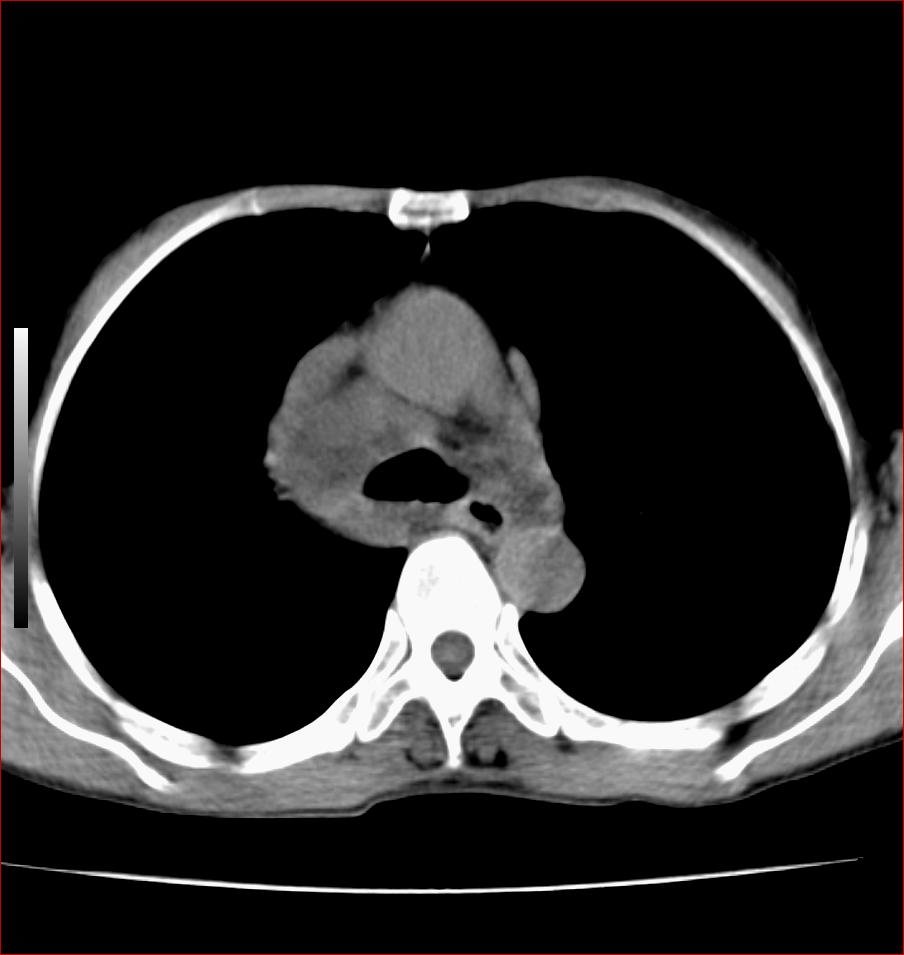

标题: CT17110:F56Y,纵隔囊肿;胸腺?淋巴?请各位老师看看 [打印本页]

标题: CT17110:F56Y,纵隔囊肿;胸腺?淋巴?请各位老师看看

女性患者 56 咽痛伴声嘶10+天入院。

纵隔囊肿,气管来源可能性大

病变紧贴气管右壁,两者相互压迫,考虑支气管囊肿!

纵隔前肠性囊性,支气管囊肿可能性大